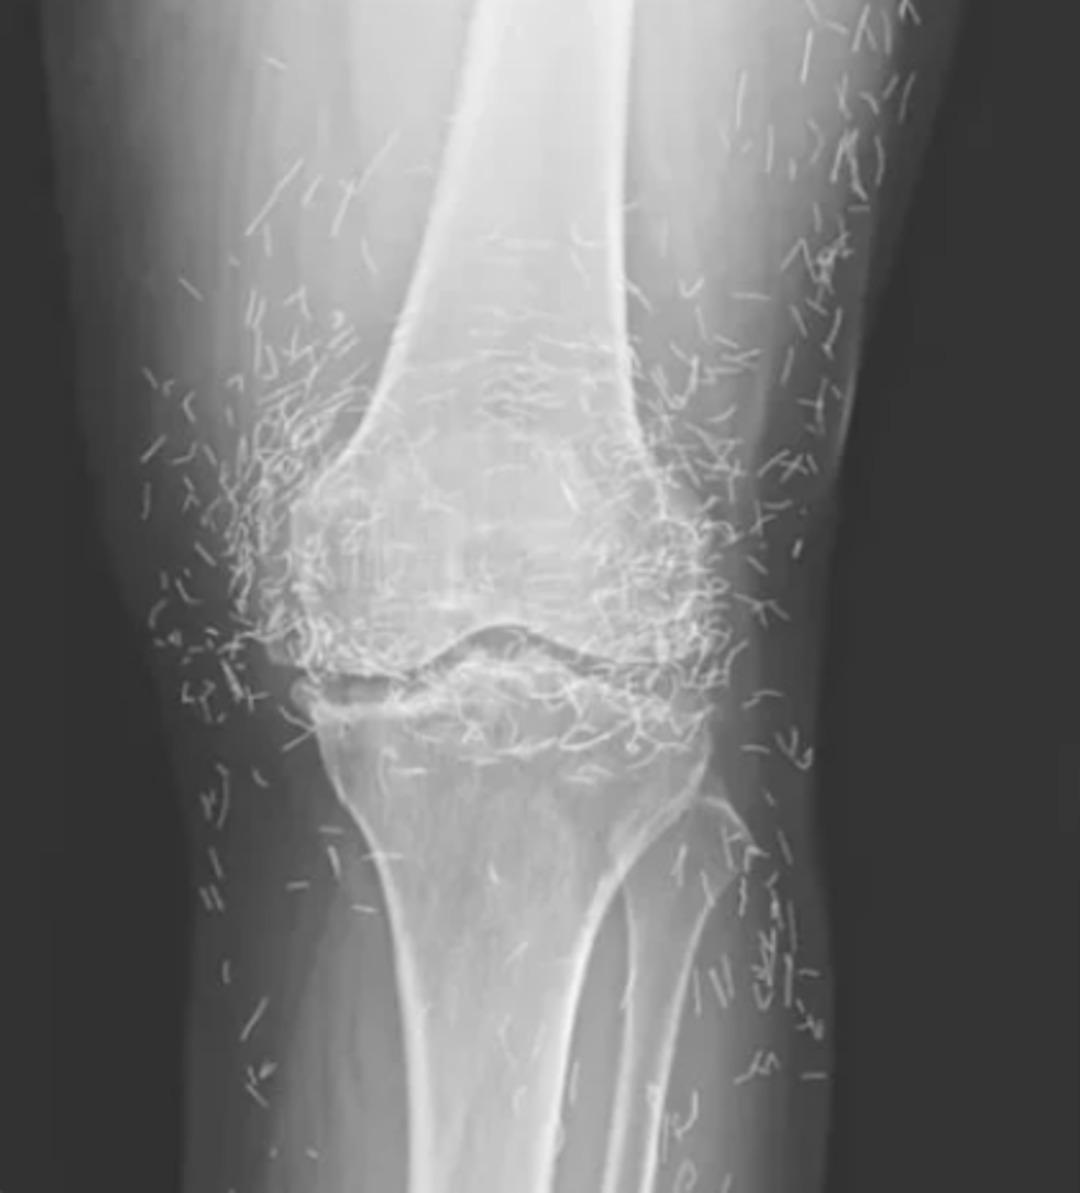

Güney Kore’de 65 yaşındaki bir kadın, şiddetli diz ağrısı şikâyetiyle hastaneye başvurdu. Yapılan röntgende yüzlerce altın iplik ile birlikte kemiklerde sertleşme, kalınlaşma ve mahmuz benzeri çıkıntılar tespit edildi.

Kadının daha önce kireçlenme (osteoartrit) tanısı aldığı, ancak ağrı kesici ve steroid tedavilerinden sonuç alamadığı öğrenildi. Mide rahatsızlığı nedeniyle ilaçları bırakan kadın, haftada birkaç kez “altın iplik akupunkturu” seanslarına katılmaya başladı.

Bu yöntemde, kısa ve steril altın iplikler deri altına yerleştirilerek sürekli uyarım amaçlanıyor. Doktorlar, ipliklerin vücutta bilinçli olarak bırakıldığını ancak zamanla yer değiştirebileceğini, kist oluşumu ve enfeksiyon gibi riskler taşıdığını belirtiyor.

Altın iplik akupunkturu, Asya’da kireçlenme ve iltihaplı romatizma tedavisinde yaygın kullanılıyor. Ancak uzmanlar, bu yöntemin etkinliğini destekleyen yeterli bilimsel kanıt olmadığını vurguluyor. Ayrıca bazı hastaların bu tedavi nedeniyle gerekli tıbbi müdahaleleri geciktirdiği uyarısı yapılıyor.

Daha önceki vakalarda, altın ipliklerin vücutta hareket ederek başka bölgelere ulaştığı ve enfeksiyona neden olduğu bildirildi. Ayrıca iplikler, röntgen ve MR gibi görüntüleme yöntemlerini zorlaştırabiliyor, hatta damar hasarına yol açma riski taşıyor.